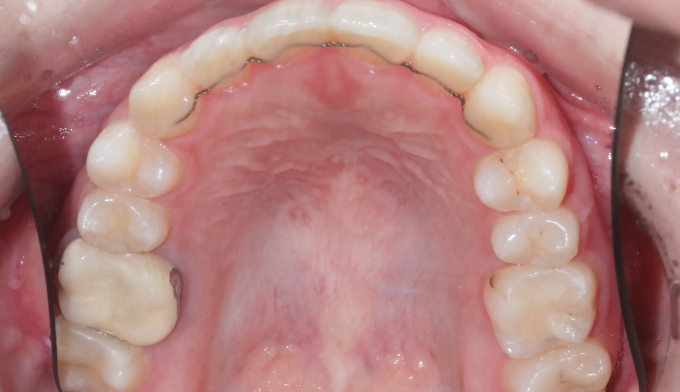

앞니 하나만 뒤로 들어간 경우, 해당 치아만 앞으로 빼내면 되는 간단한 교정이라고 생각하기 쉽습니다.

하지만 해당 치아가 뒤로 들어가면서 전체적인 치열이 한쪽으로 쏠리는 비대칭이 나타났기 때문에 이를 모두 해결하기 위해서는 전체교정을 통한 긴 치료기간이 필요합니다.

안쪽으로 들어간 앞니 양쪽으로 치열을 밀어서 공간을 확보해주고 앞니를 재위치 시켰습니다.

추가로 한쪽으로 틀어진 치열들도 위아래 중심선을 맞추어주었습니다.

총 치료기간은 17개월입니다.